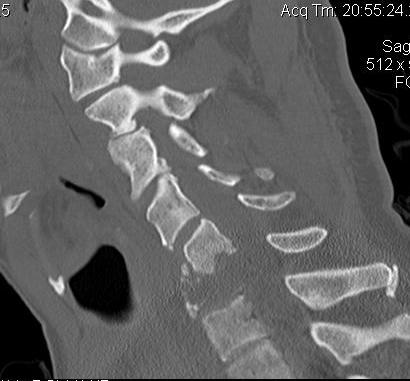

CT Scan

Define

- bony abnormality

- deformity

- potential instability

Cervical Lesions